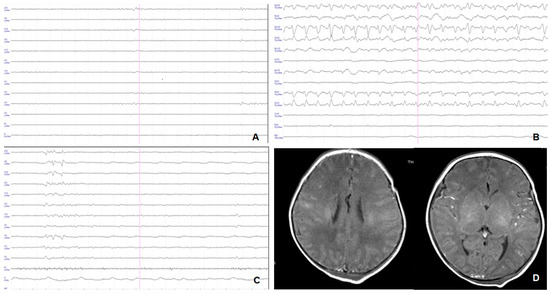

| p-EEG -Normal -Mild abnormalities -Moderate abnormalities -Severe abnormalities -Inactive p-EEG | 10 (7.2%) 47 (33.8%) 43 (30.9%) 35 (25.2%) 4 (2.9%) | 0 0 43 (52.4%) 35 (42.7%) 4 (4.9%) | 10 (17.5%) 47 (82.5%) 0 0 0 | <0.0001 * |

| p-EEG -Moderate p-EEG abnormalities -Severe p-EEG abnormalities -Inactive p-EEG | 0 7 (77.8%) 2 (22.2%) | 43 (58.9%) 28 (38.4%) 2 (27.4%) | 0.0002 * |

| p-EEG under age 6 h Normal p-EEG Mild p-EEG abnormalities Moderate p-EEG abnormalities Severe p-EEG abnormalities Inactive p-EEG | 0 0 42 (63.6%) 24 (36.4%) 0 | 0 0 1 (14.3%) 5 (71.4%) 1 (14.3%) | 0 0 0 7 (77.8%) 2 (22.2%) | <0.0001 * |

| p-EEG at age 24 h Normal p-EEG Mild p-EEG abnormalities Moderate p-EEG abnormalities Severe p-EEG abnormalities Inactive p-EEG | 0 15 (22.7%) 42 (63.6%) 9 (13.6%) 0 | 0 1(14.3%) 2(28.6%) 4 (57.1%) 0 | 0 0 1 (11.1%) 6 (66.7%) 2(22.2%) | <0.0001 * |

| p-EEG at age 48 h Normal p-EEG Mild p-EEG abnormalities Moderate p-EEG abnormalities Severe p-EEG abnormalities Inactive p-EEG | 0 34 (51.5%) 29 (43.9%) 3 (45.5%) 0 | 0 2 (28.6%) 1 (14.3%) 4 (57.1%) 0 | 0 0 1 (11.1%) 8 (88.9%) 0 | <0.0001 * |

| p-EEG at age 72 h Normal p-EEG Mild p-EEG abnormalities Moderate p-EEG abnormalities Severe p-EEG abnormalities Inactive p-EEG | 2 (3.03%) 52 (78.79%) 12 (18.2%) 0 0 | 1(14.3%) 2 (28.6%) 4(57.1%) 0 0 | 0 0 3 (33.3%) 6 (66.7%) 0 | <0.0001 * |

| p-EEG -Normal -Mild abnormalities -Moderate abnormalities -Severe abnormalities -Inactive p-EEG | 10 (14.1%) 47 (66.2%) 10 (14.1%) 4 (4.6%) 0 | 10 (17.5%) 47 (82.5%) 0 0 0 | 0 0 10 (71.4%) 4 (18.6%) 0 | 0.001 * |